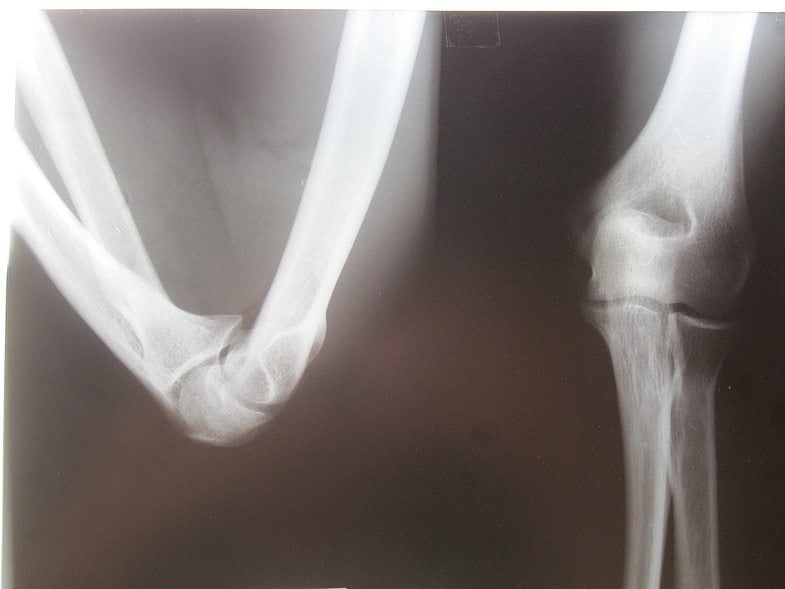

Артриты встречаются примерно в 10% всех случаев болей в области локтя. Они имеют тенденцию быстро распространяться на другие суставы. Так моноартрит переходит в полиартрит. Для диагностики заболевания врач проводит с пациентом беседу для выяснения всех деталей клинической картины. Производится осмотр с пальпацией. Для уточнения локализации воспаления делают рентген в двух проекциях: прямой и боковой. Чтобы выяснить степень воспаления, сдают анализ крови.

Если рентгенографии оказывается недостаточно, то проводят ультразвуковое исследование, делают компьютерную или магнитно-резонансную томографии. Дополнительно используются атро- и термографии (обследование тепловизором). Также возможна пункция содержимого синовиальной сумки, биопсия тканей для выявления этиологии заболевания. Анализируя химический состав извлеченного содержимого, можно установить возбудителей воспалительного процесса.

На первом прием врач осматривает пациента, выслушивает жалобы, изучает анамнез. Он измеряет амплитуду активных и пассивных движений для определения степени функциональных расстройств. Выставить окончательный диагноз позволяют результаты инструментальных исследований:

- рентгенография локтевого сустава в прямой и боковой проекциях;

- КТ или МРТ;